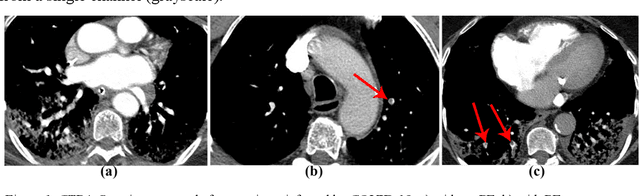

Abstract:The main objective of this work is to utilize state-of-the-art deep learning approaches for the identification of pulmonary embolism in CTPA-Scans for COVID-19 patients, provide an initial assessment of their performance and, ultimately, provide a fast-track prototype solution (system). We adopted and assessed some of the most popular convolutional neural network architectures through transfer learning approaches, to strive to combine good model accuracy with fast training. Additionally, we exploited one of the most popular one-stage object detection models for the localization (through object detection) of the pulmonary embolism regions-of-interests. The models of both approaches are trained on an original CTPA-Scan dataset, where we annotated of 673 CTPA-Scan images with 1,465 bounding boxes in total, highlighting pulmonary embolism regions-of-interests. We provide a brief assessment of some state-of-the-art image classification models by achieving validation accuracies of 91% in pulmonary embolism classification. Additionally, we achieved a precision of about 68% on average in the object detection model for the pulmonary embolism localization under 50% IoU threshold. For both approaches, we provide the entire training pipelines for future studies (step by step processes through source code). In this study, we present some of the most accurate and fast deep learning models for pulmonary embolism identification in CTPA-Scans images, through classification and localization (object detection) approaches for patients infected by COVID-19. We provide a fast-track solution (system) for the research community of the area, which combines both classification and object detection models for improving the precision of identifying pulmonary embolisms.